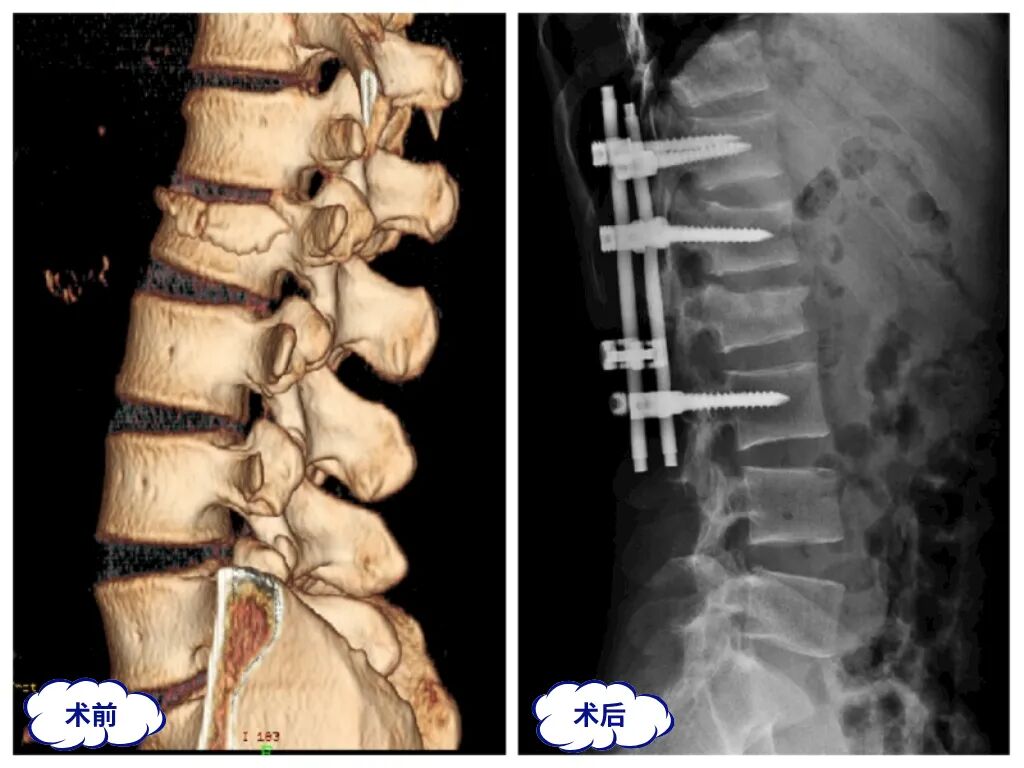

脊柱专业